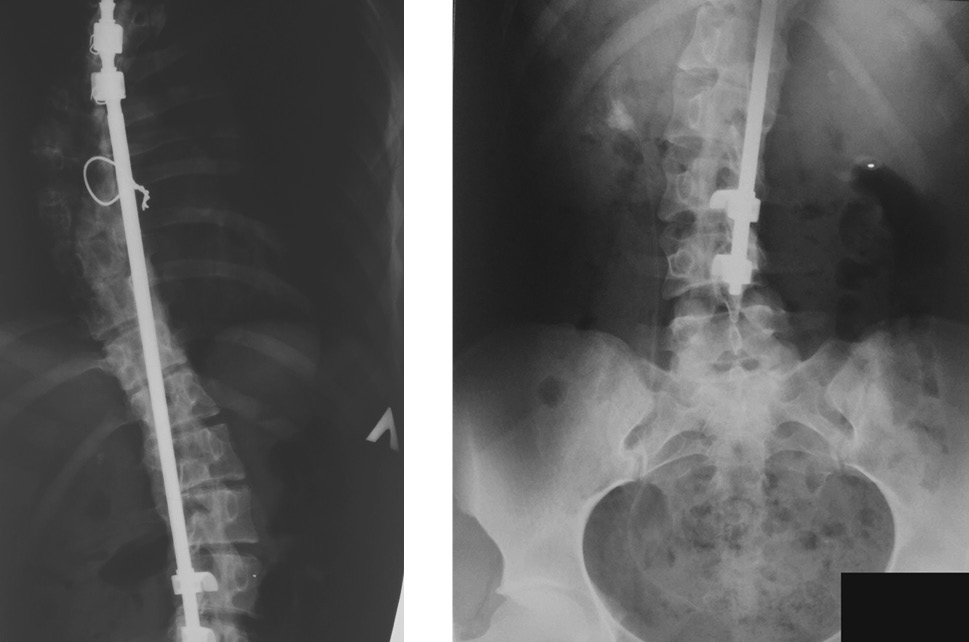

Из анамнеза известно, что пациентка страдает диспластическим правосторонним грудным сколиозом IV степени. В 2000 г., в возрасте 15 лет, у пациентки выполнены дискапофизэктомия на вершине деформации, передний корпородез, наложено краниотибиальное вытяжение. В 2001 г. (через 3 мес. от первого оперативного вмешательства) были проведены коррекция и стабилизация деформации позвоночника эндокорректором института им. Г.И. Турнера с боковыми проволочными тягами (Th4,5–L2,3), задний спондилодез аллотрансплантатами. Результат лечения представлен на рентгенограммах (рис. 2).

Рис. 2. Рентгенограммы грудного и поясничного отделов позвоночника пациентки С. (в прямой проекции)

Fig. 2. Radiographs of the thoracic and lumbar spine of patient S. (performed in the direct projection)